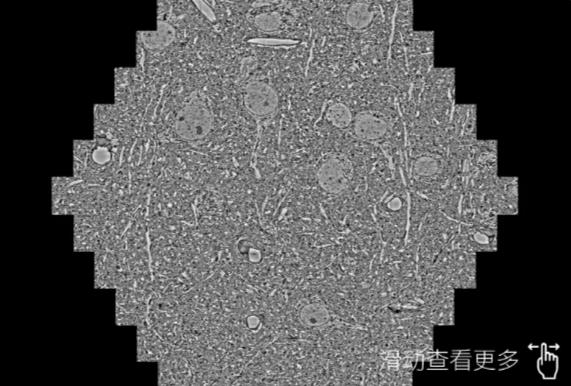

鼠脑切片。左图使用山南蔡司山南扫描电镜MultiSEM706对165μmx143pm面积区域成像,耗时仅需1.5秒。右图为鼠脑切片中30μm区域放大效果。样品由芝加哥大学B.Kasthuri提供。

使用蔡司高速山南扫描电镜MultiSEM对1mm²人脑皮层组织进行高分辨成像,并对其中的各种细胞结构进行三维重构分析。左图展示了2x3mm²组织平面中锥体神经元的三维重构效果。右图显示了局部体积神经元三维重构。图像由哈佛大学chtman实验室提供,渲染图由D. Berger 制作。